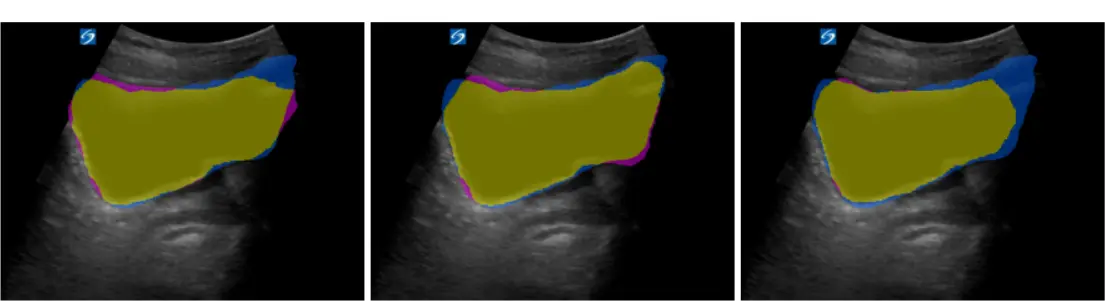

• Led domain-aligned transfer learning for NIH-funded bladder segmentation project. Pretrained U-Net and SimSiam SSL encoders on 9.2K thyroid/breast ultrasound images, achieving 95.99% Dice on downstream task.

• Enabled edge deployment via 4-bit PTQ with 7x robustness improvement over ImageNet initialization.

• Built automated data pipeline with PyTorch and OpenCV: extracted, preprocessed, and segmented 486 clinical images from ultrasound videos with augmentation and quality validation frameworks.

Ultrasound Bladder Segmentation

NIH-funded project: pretrained U-Net encoders on 9.2K ultrasound images, achieving 7x robustness improvement in 4-bit quantization for edge deployment.

SSL OpenCV Model Quantization